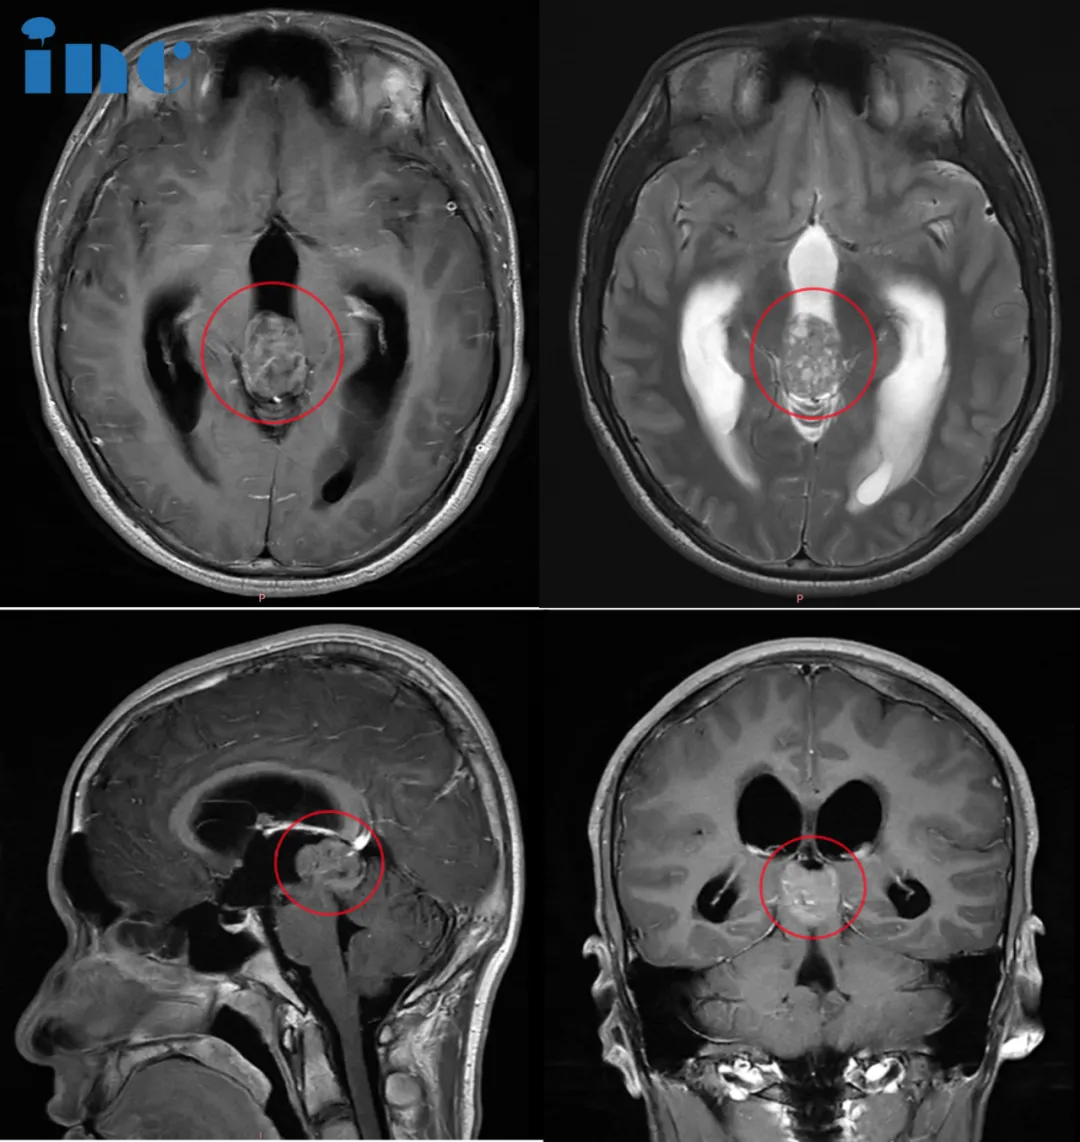

CASE 1:36岁女性-松果体区肿瘤

病史摘要:晴晴在2021年11月因鼻炎进行颅脑CT检查,显示松果体占位性病变,当时大小为16*15*12mm,无特别神经功能障碍,随后进行颅脑核磁MRI,医生建议先观察3个月。观察结束后进行复查,建议手术治疗并告知相关风险。考虑到手术风险,晴晴选择继续保守治疗。2022年9月再次复查,肿瘤伴幕上脑积水。除了偶有眩晕、脑涨,其他症状并不明显,晴晴还是选择了保守。2023年3月再次复查时,肿瘤竟然长大了18*18*15mm,并出现幕上脑积水。临床症状不变化,医生建议再持续观察3-6月,但最终需要手术治疗。

手术过程:2023年6月,首都医科大学附属北京天坛医院正式引进INC德国巴特朗菲教授作为其神经外科外籍专家,在天坛医院手术团队的配合下,巴教授成功主刀完成这台疑难脑肿瘤示范教学手术,手术全切肿瘤。

术后情况:术后即清醒,无新发神经损伤。术后1周后,术后病理结果为WHO2-3级中分化松果体实质肿瘤,根据巴教授建议患者及时进行放化疗,巴教授及时全切手术为后续放化疗争取到了更好的结果。